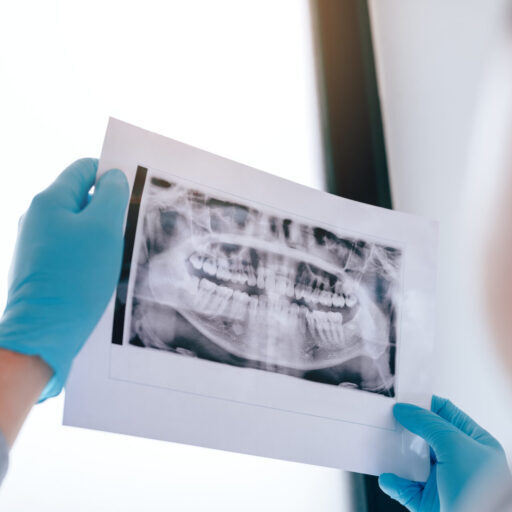

Enjoy our special offer on an adult check up and clean at our Cannon Hill dental clinic. This package includes a dental exam, professional clean, two standard X rays and a fluoride treatment.